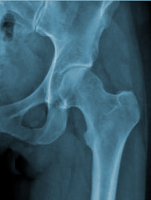

HANCHE - Articulation COXO-FEMORALE

Généralités

C'est une énarthrose (3 ddl) qui

unit la cuisse au bassin : l'os coxal (old.

os iliaque) à l'extrémité proximale du fémur

(c'est l'articulation proximale du membre inférieur). Entre les deux

pièces osseuses est tendu le ligament de la tête fémorale. Cette

articulation transmet le poids du corps au membre inférieur.

Surfaces Articulaires

- En DH : sur le fémur, la tête fémorale représente les 2/3 d'une

sphère pleine (20 à 25 mm de rayon). Elle est recouverte de cartilage

(plus épais en HT qu'en BAS) à l'exception de la fovéa d'insertion du

ligament. Elle regarde en DD, en HT et en AV (15° par rapport au plan

frontal). La tête fémorale est reliée à la diaphyse par le "col du

fémur".

- En DD : sur la face externe de l'os coxal, dans son segment moyen,

au dessus du trou obturateur : l'acétabulum

(old. cavité cotyloïde). C'est une cavité hémisphérique limitée

dans son pourtour par un sourcil ou lèvre (plus marqué en HT) et par

l'échancrure ischio-pubienne en BAS. Elle présente 2 régions : à la

périphérie, une surface semi-lunaire encroûtée de cartilage (en forme

de croissant concave vers le BAS et se terminant par 2 cornes :

antérieure et postérieure) et au centre, la fosse acétabulaire

(old. arr. fond) non recouverte de cartilage, non articulaire

(remplie d'un paquet adipeux).